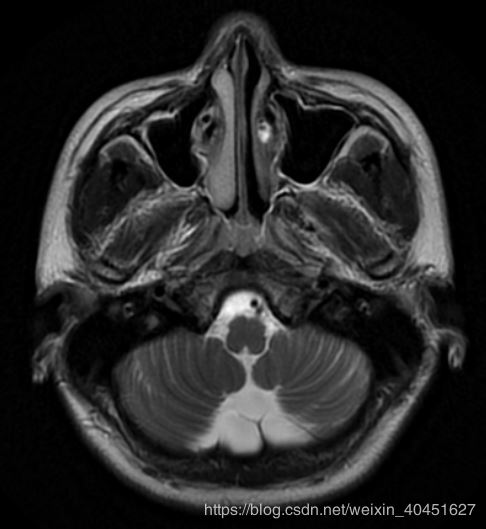

效果如图所示:

但真实的图像是:

显然颜色是有区别的.导致这种差别的原因是pyplot函数使用的cm也就是"color map" 是简单的"bone" 并不能满足医学图像的要求.